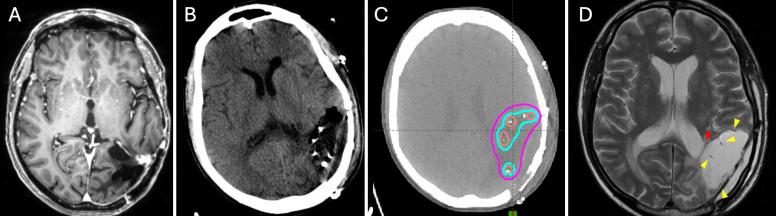

Reirradiation of recurrent high-grade gliomas (HGGs) with external beam radiation therapy is limited by the risk of radiation necrosis (RN). Intraoperative brachytherapy offers a localized radiation approach that minimizes RN risk while maintaining tumor control. However, seed migration has historically limited its use in periventricular regions. The authors present 3 cases of recurrent periventricular HGG (2 IDH-wildtype, MGMT promoter-methylated, EGFR-amplified WHO grade 4 glioblastoma and 1 WHO grade 3 astrocytoma) in which a three-layered barrier was created between the ventricular lining and tumor cavity to prevent seed migration, enabling successful brachytherapy.

OBSERVATIONS

Following maximal safe resection, a three-layered patch separated the resection cavity from the ventricle prior to cesium-131 (131Cs) brachytherapy. Patient 1 received suture-stranded 131Cs (20 seeds), while patients 2 and 3 received 131Cs GammaTile (6 tiles, 4 seeds per tile). A three-layered barrier was formed using Gelfoam, Surgicel, and Adherus. At a median 22-month (range 11-24 months) follow-up, MRI confirmed no seed migration and seeds remained in the cavity. There were no complications associated with the barrier placement.